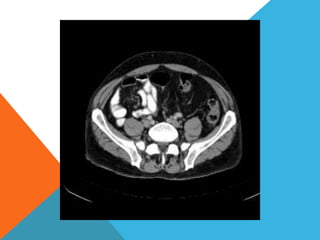

El paciente presentó síntomas de sangrado digestivo y pérdida de peso. Exámenes revelaron gastritis crónica asociada a H. pylori. Un tumor fue descubierto en una colonoscopia normal. La cirugía removió un tumor fibroide solitario, una rara neoplasia mesenquimal que usualmente crece lento y tiene bajo potencial de malignidad. El pronóstico después de la remoción quirúrgica es generalmente bueno.